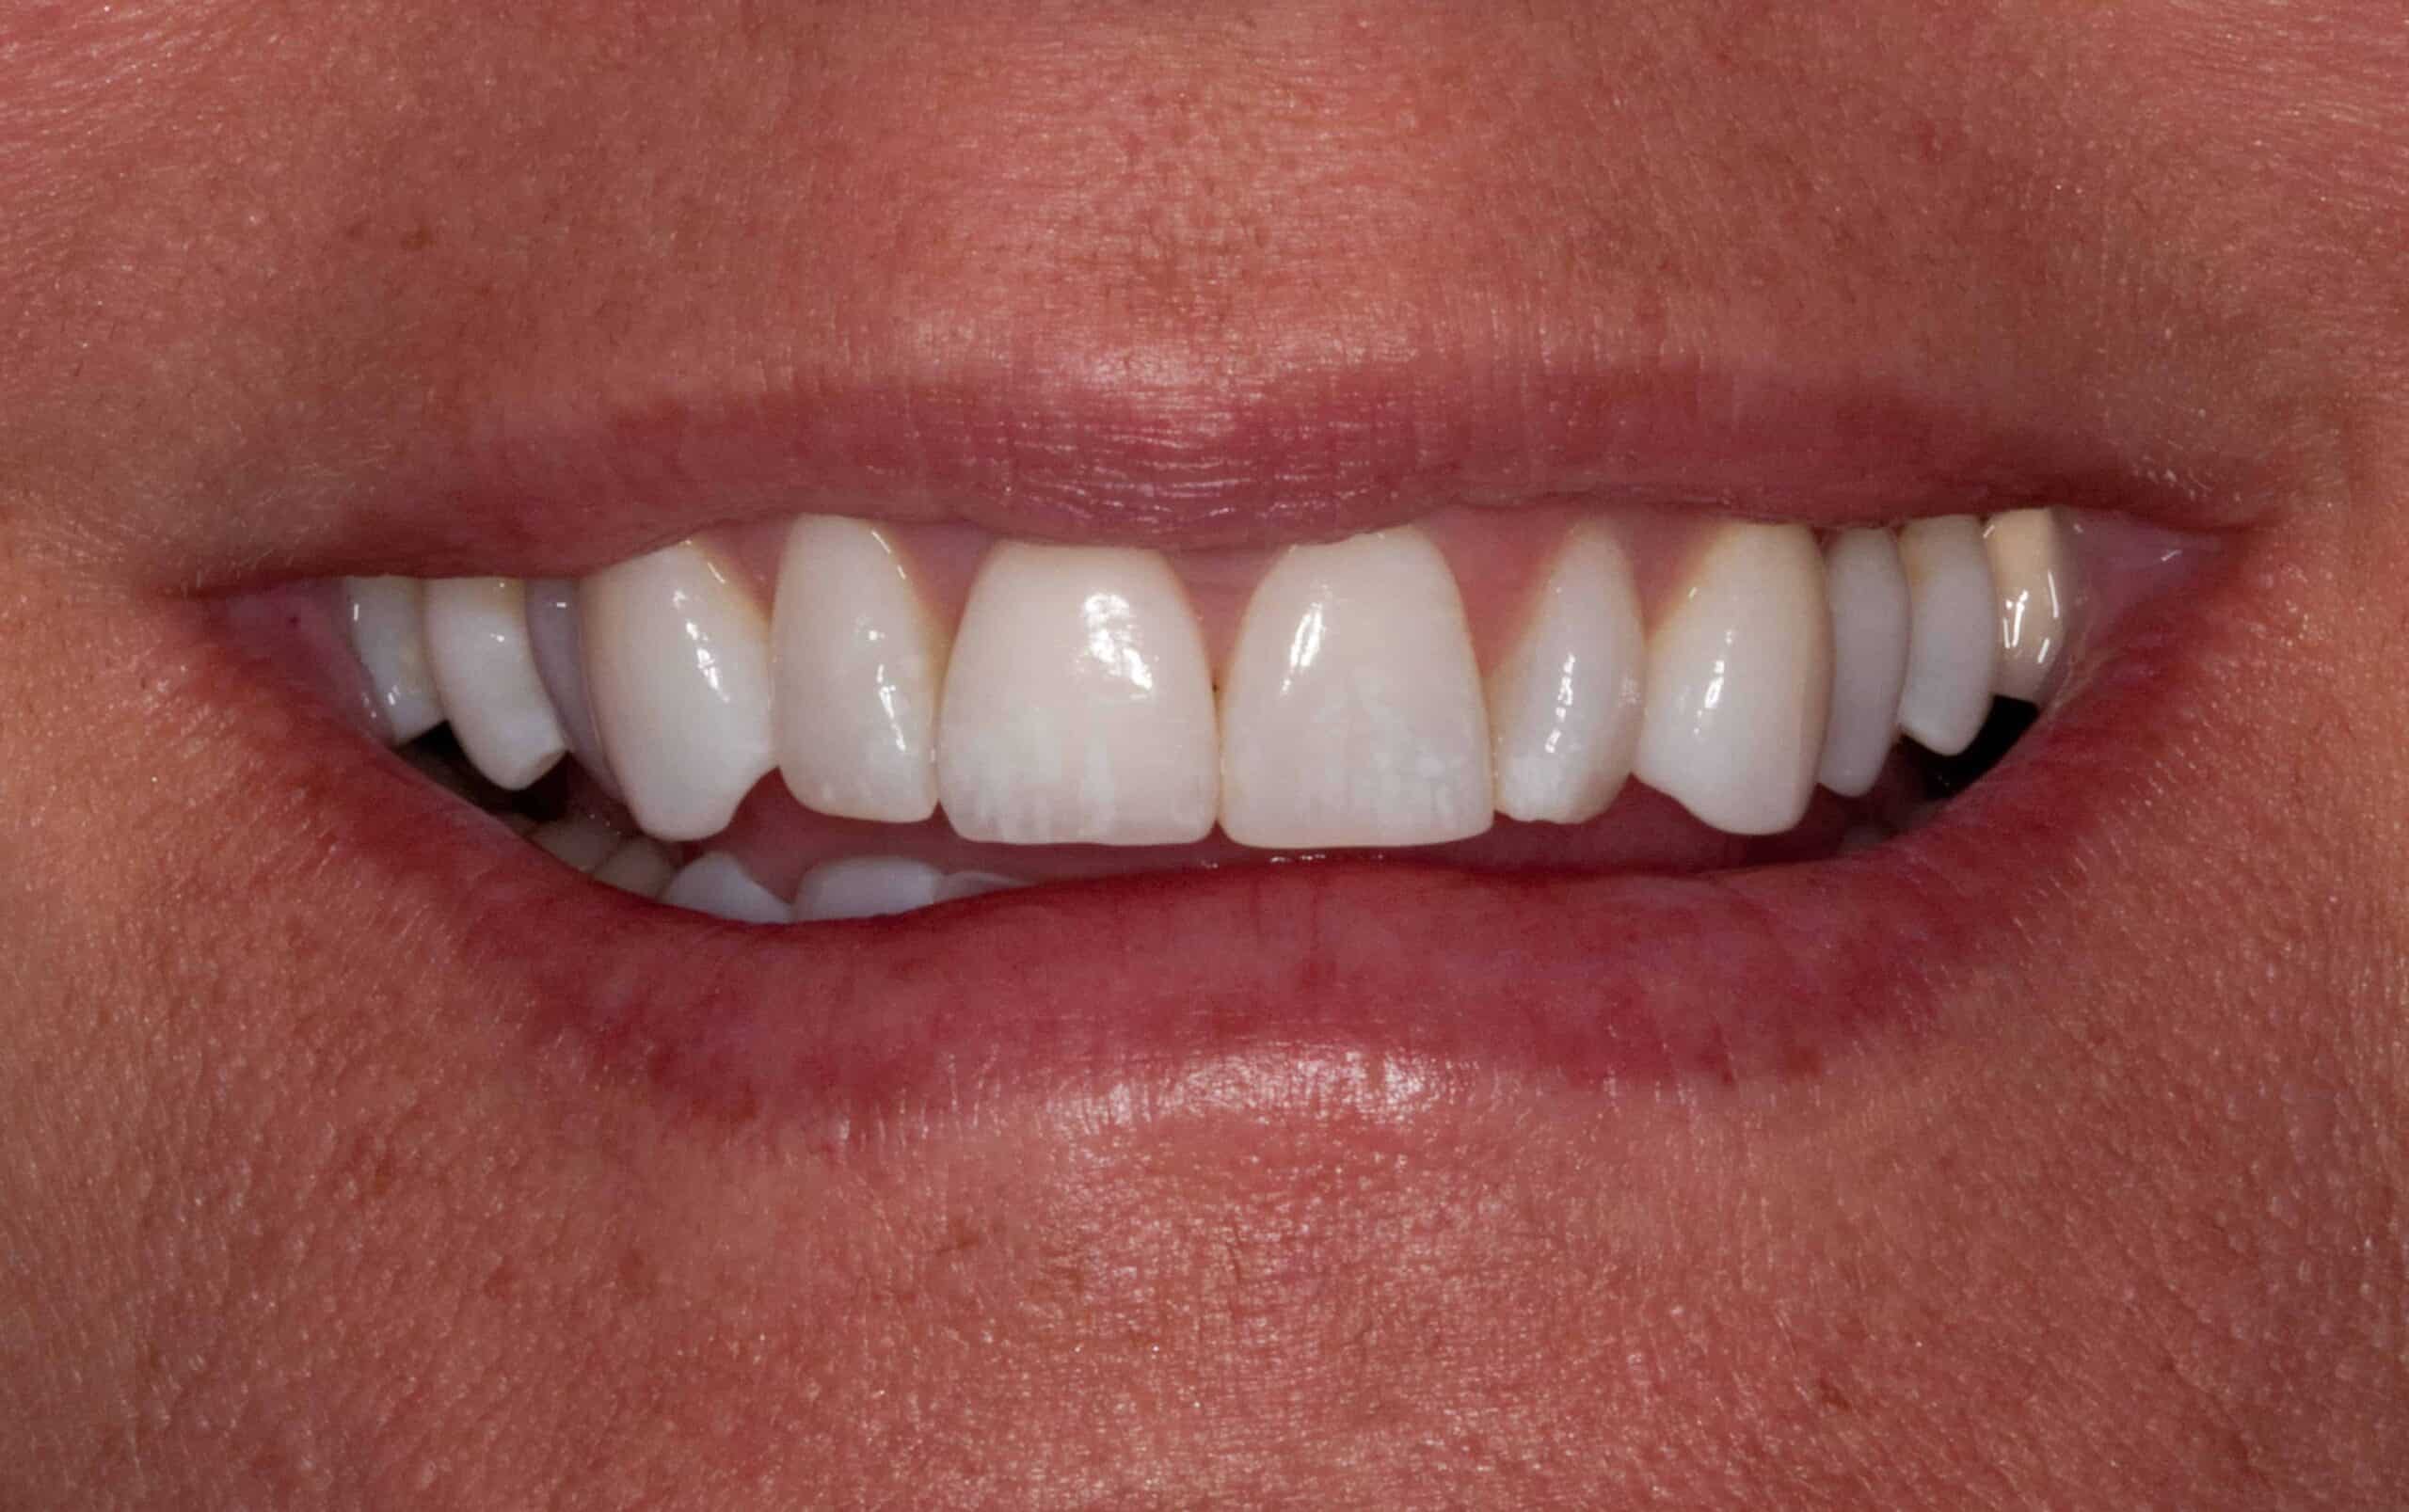

After: Single, all-ceramic crown attached to an all-ceramic, CAD-CAM designed and generated abutment (implant post). A delayed treatment approach was undertaken: tooth/root removal and grafting; 4 months healing; interim removable partial tooth replacement; implant placement; 6 months healing; proto-type (transitional fixed) implant crown, then the definitive implant restoration. The new tooth blends in perfectly with the natural, adjacent teeth.